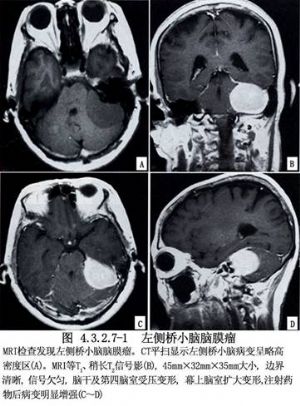

小脑脑桥角是颅内脑膜瘤多发部位之一,约占颅内脑膜瘤的10%左右。肿瘤的基底附着于乙状窦、岩上窦、岩下窦或颈内静脉孔附近。其部位贴近小脑幕,位于小脑桥脑角前上或外侧。肿瘤增大常累及邻近的颅神经并压迫小脑与脑干。有的脑膜瘤向上经小脑幕裂孔向颅中窝生长至鞍背的后方。此类脑膜瘤具有脑膜瘤的共同特点,血运十分丰富。一部分供血动脉由硬脑膜进入肿瘤基底部,一部分直接来自椎基底动脉的分支。由于肿瘤部位很深,瘤体较大并附着于硬脑膜和窦的部位,手术切除有时相当困难,必须显露良好,小心操作和止血。临床表现多有典型的小脑桥脑角综合征,类似听神经瘤,但前庭功能与听力障碍通常较听神经瘤为轻,内耳孔也不扩大(图4.3.2.7-1)。